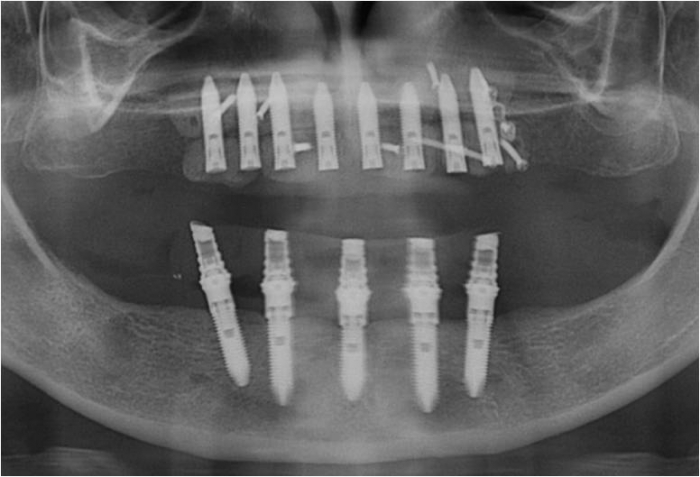

Raio X  final das próteses fixas em porcelana - Clínica Cliniface

Raio X final das próteses fixas em porcelana